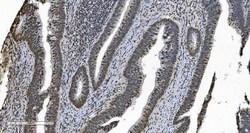

Adding 0.2 mL of distilled water will yield a concentration of 500 μg/mL. Positive Control - WB: human Jurkat whole cell, human PC-3 whole cell, human Raji whole cell, human K562 whole cell, human Caco-2 whole cell, human MCF-7 whole cell, human HL-60 whole cell, human PC-3 whole cell. IHC: human breast cancer tissue, human gastric cancer lymph node tissue, human liver cancer tissue, human ovarian serous adenocarcinoma tissue, human pancreatic cancer tissue, human placenta tissue, human rectal cancer tissue. ICC/IF: MCF-7 cell. Flow: K562 cell. Store at -20°C for one year from date of receipt. After reconstitution, at 4°C for one month. It can also be aliquotted and stored frozen at -20°C for six months. Avoid repeated freeze-thaw cycles.

| Applications | ELISA, Flow Cytometry, Immunohistochemistry (Paraffin), Western Blot, Immunocytochemistry |